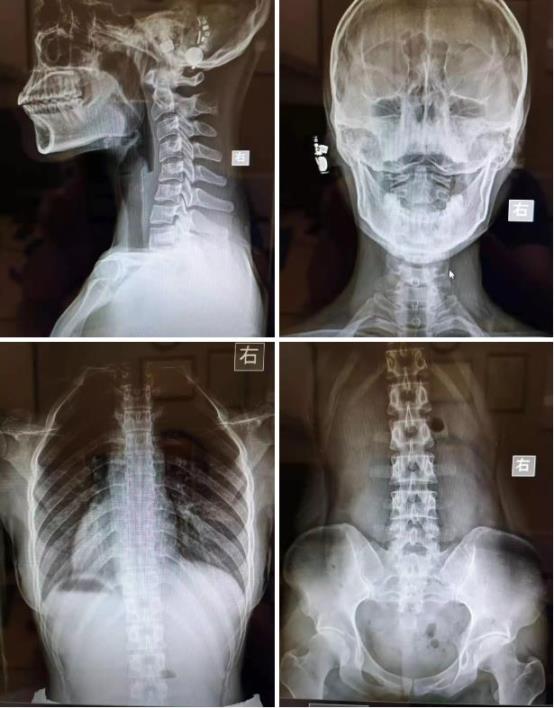

在做脊骨神经科的矫正治疗前,由于患者需要拍全脊椎X线正侧位片。

通常我们可以通过测量Cobb角,直接来确认脊椎侧弯的角度,并在合适的时间复查,以确认治疗量是否足以延缓或者纠正脊椎侧弯。